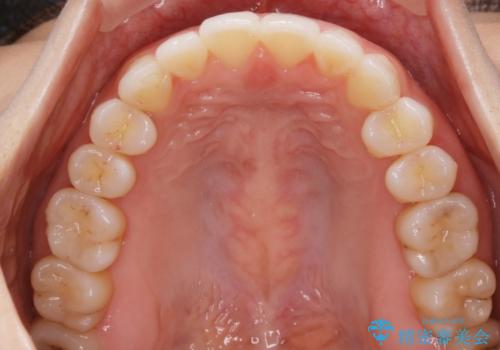

【非抜歯】前歯のガタつき マウスピースの部分矯正

- 上下の前歯の細かいガタつきの治療をご希望されて来院されました。

奥歯部分にはガタつきや噛み合わせの問題などがほとんど見られず、前歯のガタつきも軽度だったため、インビザライン ライト パッケージでの部分矯正を行うこととなりました。

今回のケースでは奥歯の噛み合わせに問題がほぼみられなかったため、前歯の位置のみに焦点を当て部分矯正を行いました。